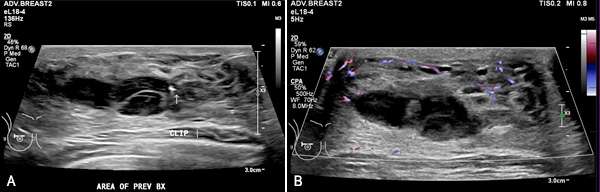

Figure 3: Greyscale (A) and color Doppler (B) images demonstrate a heterogeneous hypoechoic collection adjacent to a biopsy clip. In this patient with recent history of biopsy, this is favored to represent a small hematoma.

• Chronic hematomas often appear more heterogeneous on ultrasound compared to acute hematomas because of the breakdown of blood components and the formation of fibrin. Chronic hematomas may form a fibrous capsule as the body attempts to encapsulate and contain the hematoma. Margins may be well circumscribed but may be partially indistinct due to the presence of internal echoes. Color Doppler imaging typically exhibits reduced vascularity as the body works to reduce blood flow at the site of a bleed. In contrast to acute hematomas, chronic hematomas may exhibit posterior acoustic shadowing due to the age of blood products within the hematoma which may produce internal echoes.

• Acute hematomas typically appear as hypoechoic fluid collections as acute blood products are less reflective to ultrasound waves compared to surrounding tissues. They may have well-defined or irregular borders depending on the integrity/composition of the surrounding tissue and typically have homogenous internal echogenicity. Color Doppler imaging may be useful in identifying an active bleed if a damaged vessel is visualized adjacent to a developing hematoma. Acute hematomas sometimes exhibit posterior acoustic enhancement.